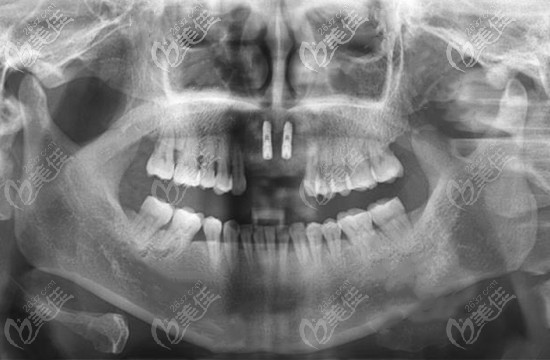

在做了咨询了解了韩国种植体的品牌后,王女士落定选择了奥齿泰种植体,之后闫路医生结合王女士的CT片以及全面的口腔检查,为其制定了种植方案。

因为是连续缺了四颗牙,考虑到其牙槽骨情况还可以,就为其种植了两颗种植体,之后安装上连桥冠。

门牙缺失四颗种植案例图片